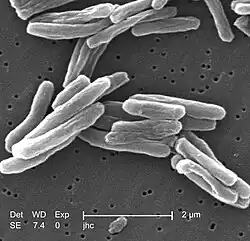

M. tuberculosis (stained red) in sputum | |

Tuberculosis is diagnosed by finding Mycobacterium tuberculosis bacteria in a clinical specimen taken from the patient. While other investigations may strongly suggest tuberculosis as the diagnosis, they cannot confirm it.

Distinctive clusters of colorless Mycobacterium tuberculosis form in this culture. | |

| Shape | rods |

A definitive diagnosis of tuberculosis can only be made by culturing Mycobacterium tuberculosis organisms from a specimen taken from the patient (most often sputum, but may also include pus, CSF, biopsied tissue, etc.).[1] A diagnosis made other than by culture may only be classified as "probable" or "presumed". For a diagnosis negating the possibility of tuberculosis infection, most protocols require that two separate cultures both test negative.[1]